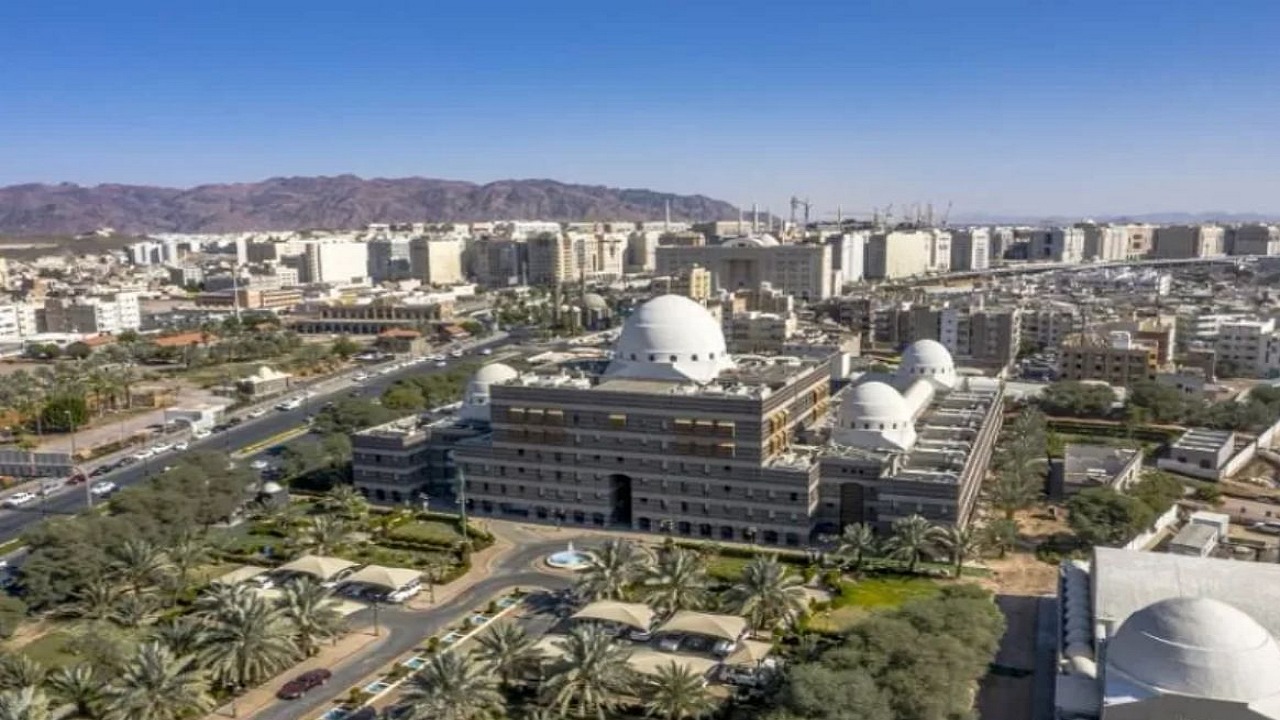

مدينة الملك سعود

مدينة الملك سعود الطبية توفر وظائف شاغرة

“سعود الطبية” تسجل أكثر من 4 آلاف حالة إنقاذ حياة في 2021

مدينة الملك سعود تعلن عن وظائف شاغرة

مدينة الملك سعود الطبية توفر أكثر من 40 وظيفة صحية شاغرة

” الملك سعود الطبية ” تكشف الحالة الصحية لمصابي شظايا صواريخ الحوثي

مدينة الملك سعود تحذر من إشعال الحطب للتدفئة مع اشتداد البرد

مدينة الملك سعود تكشف سبب إصابة طاقم تمريض بفيروس «كورونا»

فريق طبي ينقذ فتاة عشرينية من ورم عدواني يأكل في عظم الفك